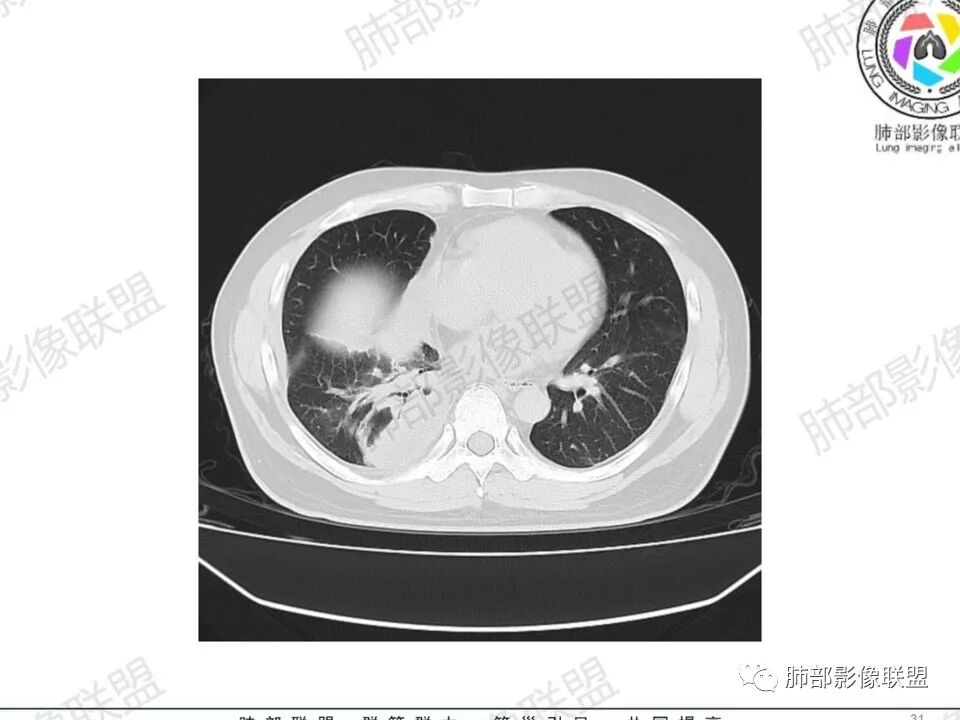

双肺多发结节,胸膜下为主,部分可见空洞。左肺上叶尖后段结节较大,分叶毛刺,周围可见长条索及小斑片影,内空洞比较光滑,内侧壁可见支气管通过。右肺下叶后基底段不张实变,后侧积液,右侧水平裂积液,右侧膈胸膜纵膈胸膜增厚积液,右侧侧胸膜肥厚,考虑1:一元金葡。2二元:金葡,左肺上叶结核。

金葡菌血流感染并双肺SPE

左手中指皮损→感染→入血→右心→肺动脉→脓毒栓子

男,45岁,左手指红肿疼痛两天,右侧胸壁疼痛伴发热12小时入院。患者急性起病,胸部CT示双肺多发结节,部分伴空洞,空洞壁较光滑,右侧胸腔积液,考虑感染性病变,金葡菌加SPE可能

感觉还是金葡入血形成SPE可能性较大,胸水+楔形影+胸膜结节

中年男性,左手中指及胸壁疼痛伴发热来诊,影像见双肺多发结节,胸膜下分布为主,部分结节可见空洞,边缘模糊。左肺上叶尖后段结节较大。右肺下叶后基底段不张实变,右侧叶间裂及右侧胸腔积液,右侧侧胸膜肥厚。考虑金葡菌感染,血播SPE。